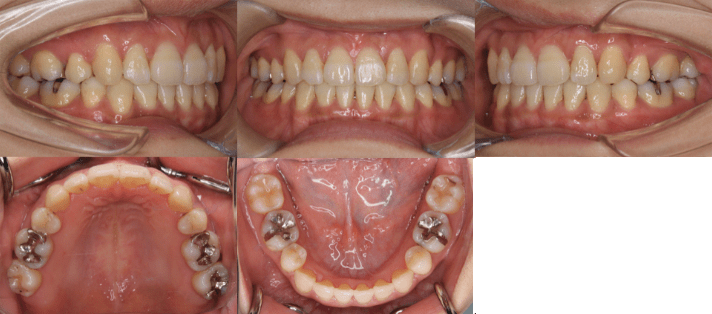

治療例③25歳7ヶ月

| 初診時年齢 | 25歳7ヶ月 |

| 主訴 | 前歯のガタガタ |

| 診断 | 交叉咬合と正中線の不一致を伴う叢生症例 |

| 抜歯の有無 | 上下左右第一小臼歯 |

| 治療内容 | 小臼歯4本を抜歯した後、マウスピース型カスタムメイド矯正歯科装置(製品名インビザライン 完成物薬機法対象外)を使用して主訴である叢生の改善を行いました。 |

| 治療期間 | 2年 通院回数21回 |

| リスク | 矯正歯科装置を付けた後しばらくは違和感、不快感、痛みなどが生じることがあります。 治療中は矯正歯科装置が歯の表面に付いているため食物が溜りやすく、また歯が磨きにくくなるため、むし歯や歯周病が生じるリスクが高まります。 歯を動かすことにより歯根が吸収して短くなることや歯肉がやせて下がることがあります。 |

| 費用 | 80万円 |

【治療前】

【治療後】